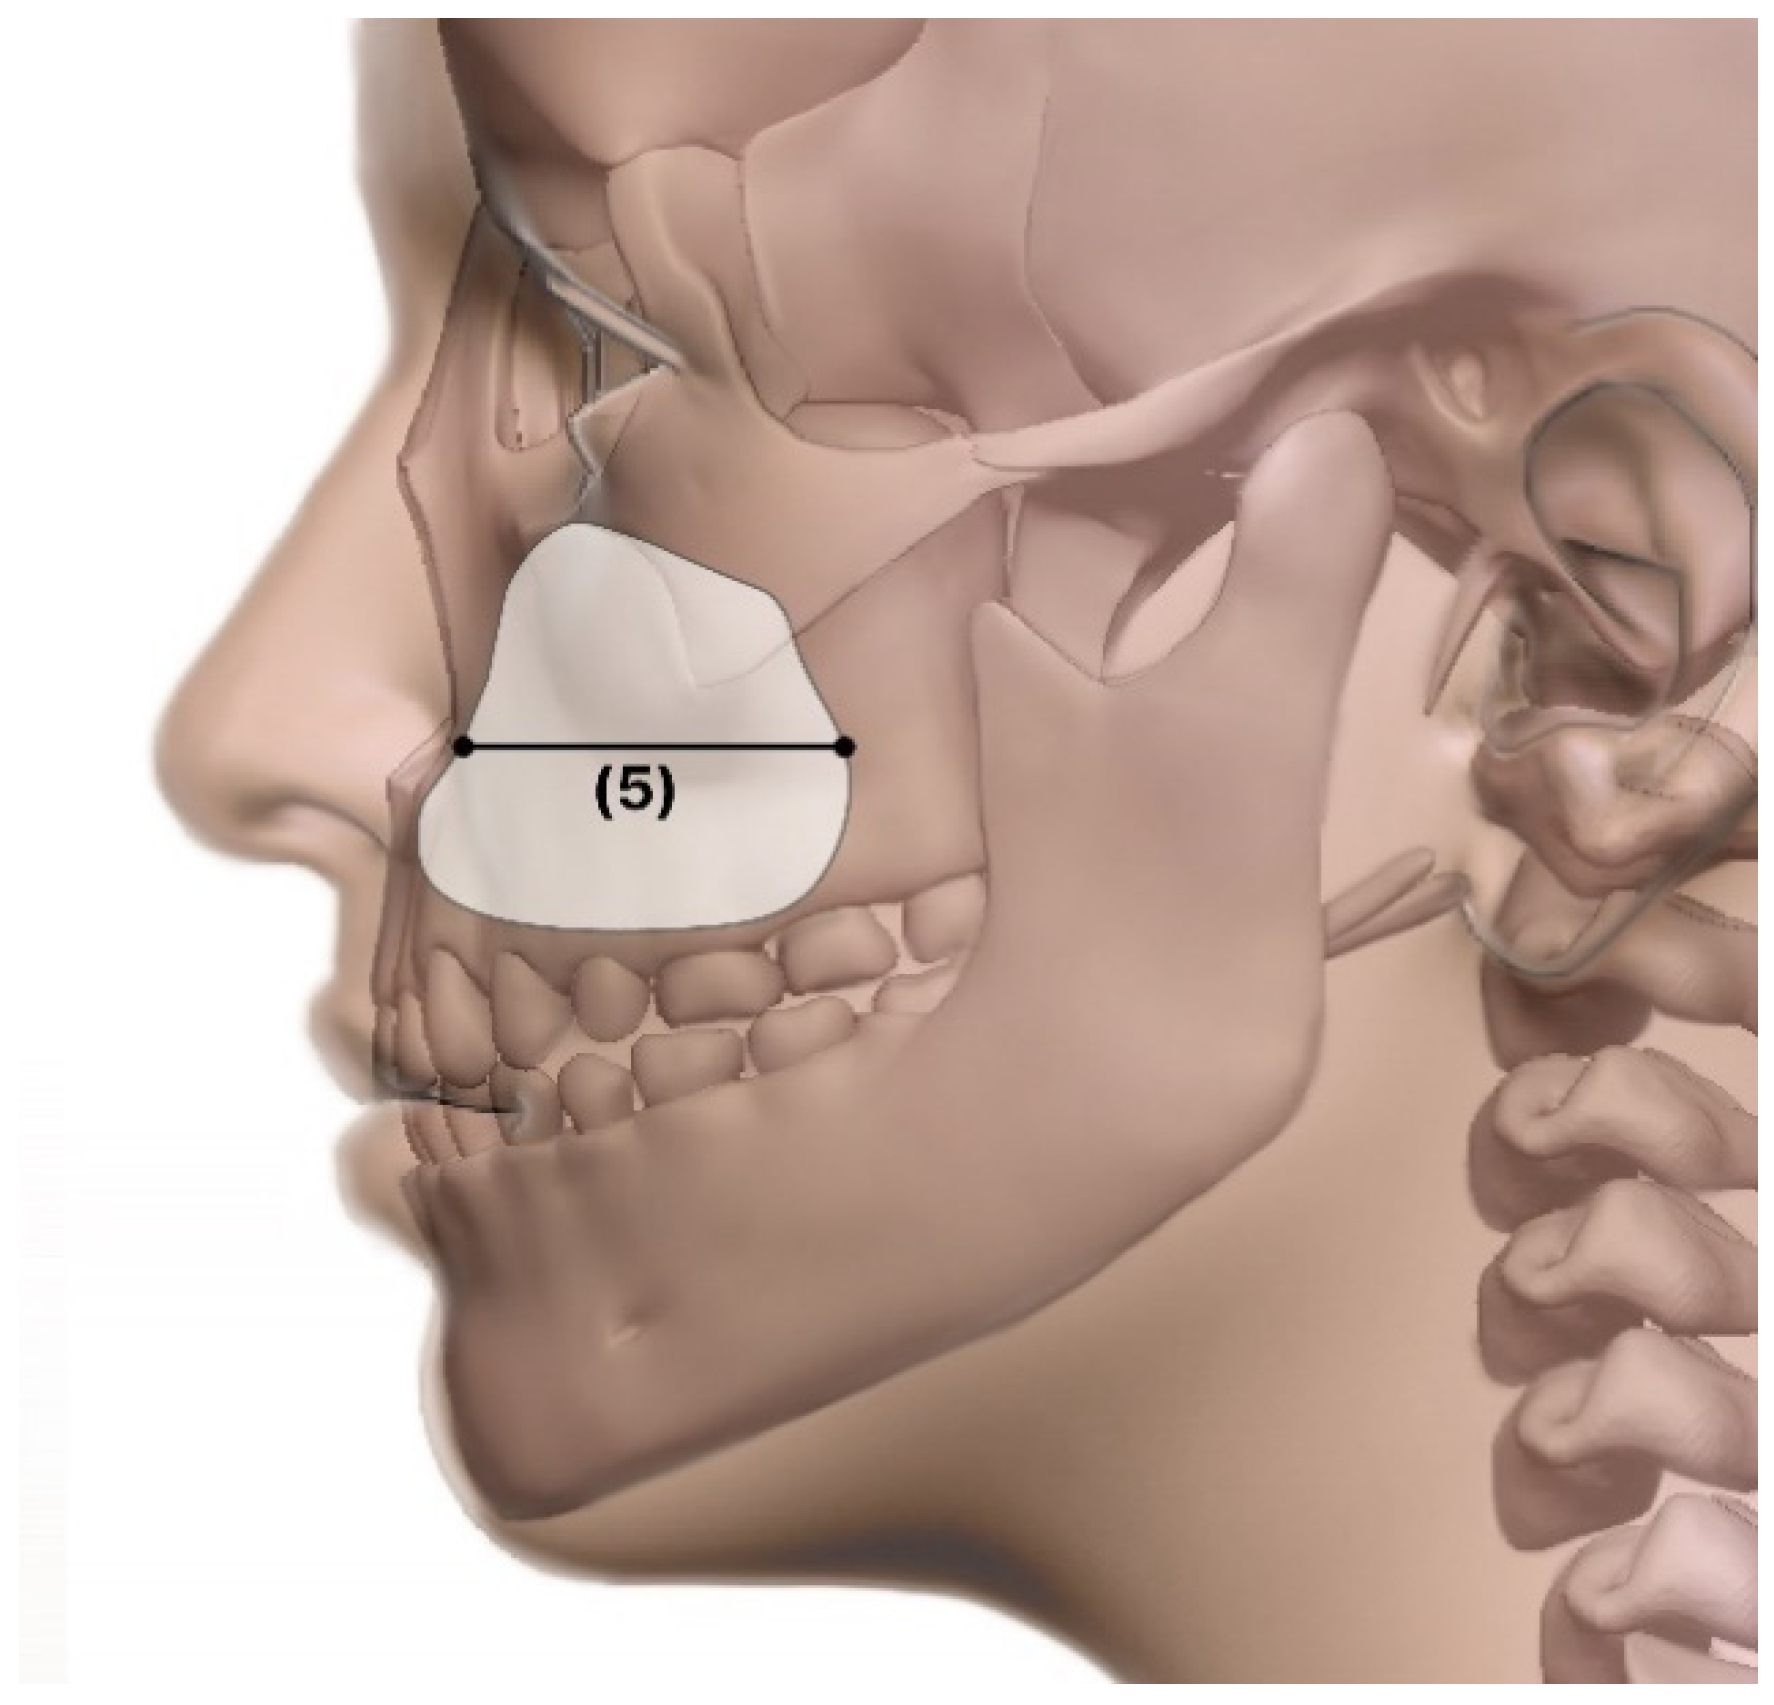

- Length: sagittal-view width